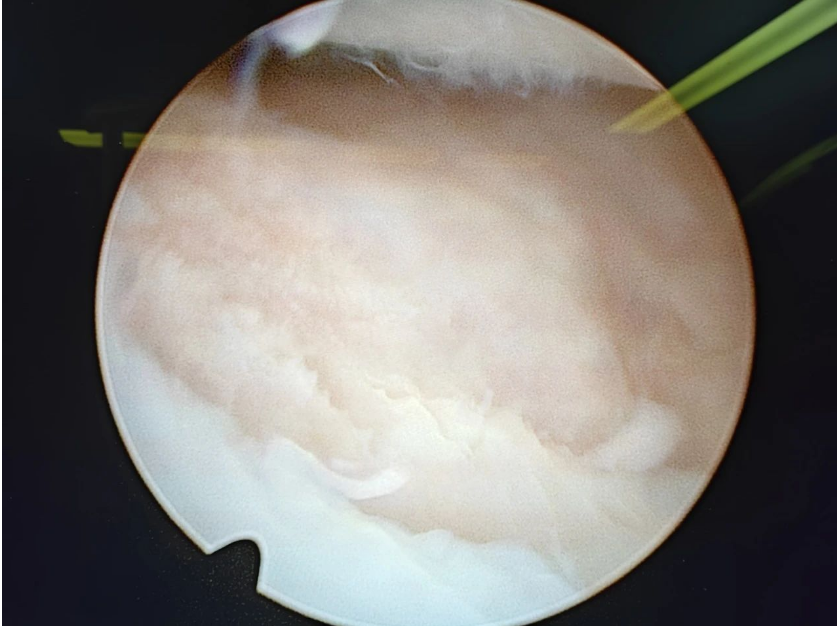

手术——张晋通过微创关节镜将缺损区域新鲜化,同时以克氏针微骨折到骨床有新鲜血液渗出,最后将胶原蛋白修复支架置入缺损区域。